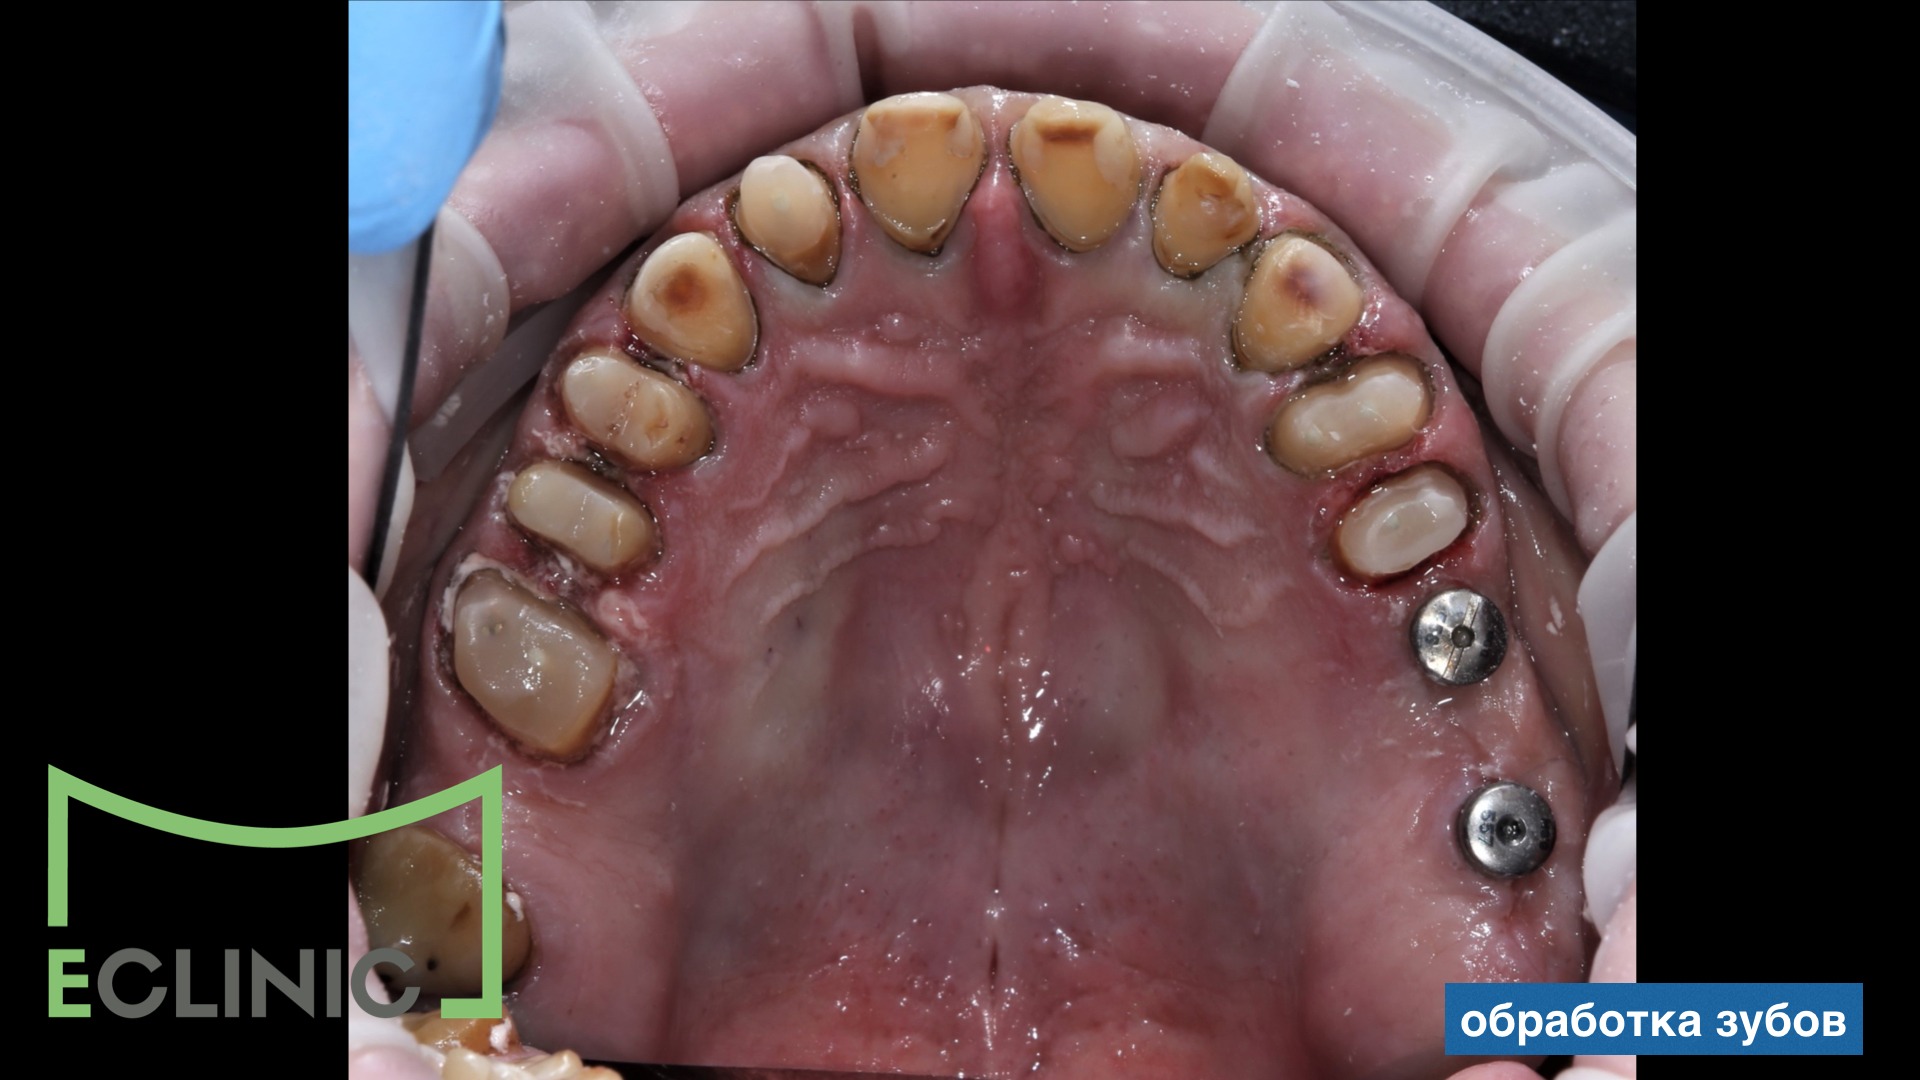

После окончания хирургического и эндодонтического этапов, для снижения мыщечного тонуса и восстановления комфортной позиции нижней челюсти была проведена сплинт терапия на миорелаксационной шине.

После этого был изготовлен мокап длительного ношения, после одобрения которого мы приступили к протезированию